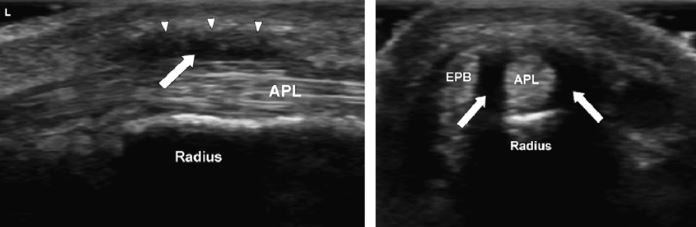

먼저 좌측은

엄지손가락 힘줄을

길게 장축으로 본 영상입니다.

힘줄 주변의 건초가

붓고, 까맣게 변해있죠?

우측은 힘줄의 단축 영상인데,

힘줄 주변 염증으로 인해

까맣게 물이 차있는 모습이 보입니다.